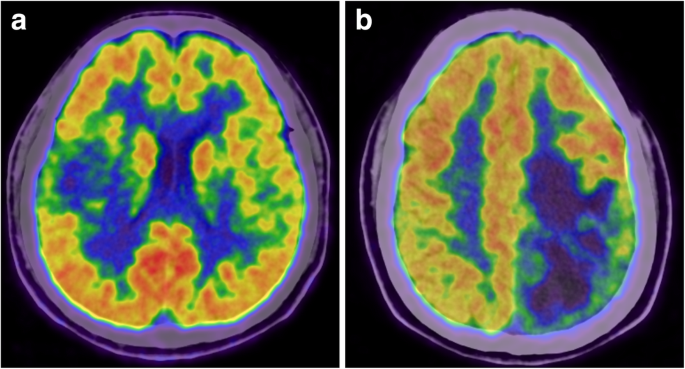

Feature selection is a core step in radiomics studies since most features have little relevance to the MGMT promoter methylation status and may overwhelm the distinguishable features if they cannot be effectively reduced. The number of final selected features also needs to be balanced according to the patient cohort size because the addition of relevant features may increase performance in the primary cohort but may also result in overfitting of the radiomics signature. In our study, the Wilcoxon rank-sum test removed 1543 of the 1561 radiomics features that were irrelevant to the MGMT promoter methylation status, and logistic regression with the L1 penalty diluted the weights, allowing selection of the final 5 radiomics features to construct the radiomics signature. Although the selected radiomics features are not visually available to nuclear medicine physicians (though they are mathematically easy to comprehend), the radiomics signature did provide additional assistance to physicians in the noninvasive molecular diagnosis of glioma (Fig. 5).

Examples of using the radiomics signature to evaluate the MGMT promoter methylation status noninvasively. A 37/M was histopathologically diagnosed with anaplastic astrocytoma with a methylated MGMT promoter (a), and a 44/M was histopathologically diagnosed with anaplastic astrocytoma with an unmethylated MGMT promoter (b). Determination of the MGMT promoter methylation status is difficult based on clinical and visually assessed imaging characteristics, but the radiomics signature demonstrated values of 0.84 (a) and 0.27 (b) in these two patients and successfully predicted their MGMT status (the cutoff value of the radiomics signature was 0.50)